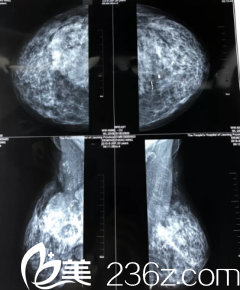

在加拿大偶然的一次日常体检中,医生发现露西的胸部有一个硬块,但是由于国外没有奥美定这种东西,他们不能分辨硬包快到底是什么。

两天后,露西便从加拿大回到了西安,第二天一早便来到医院,进行胸部奥美定注射物取出手术,医生告诉露西,取出的难度比较大,但是会尽他所能的清理干净。